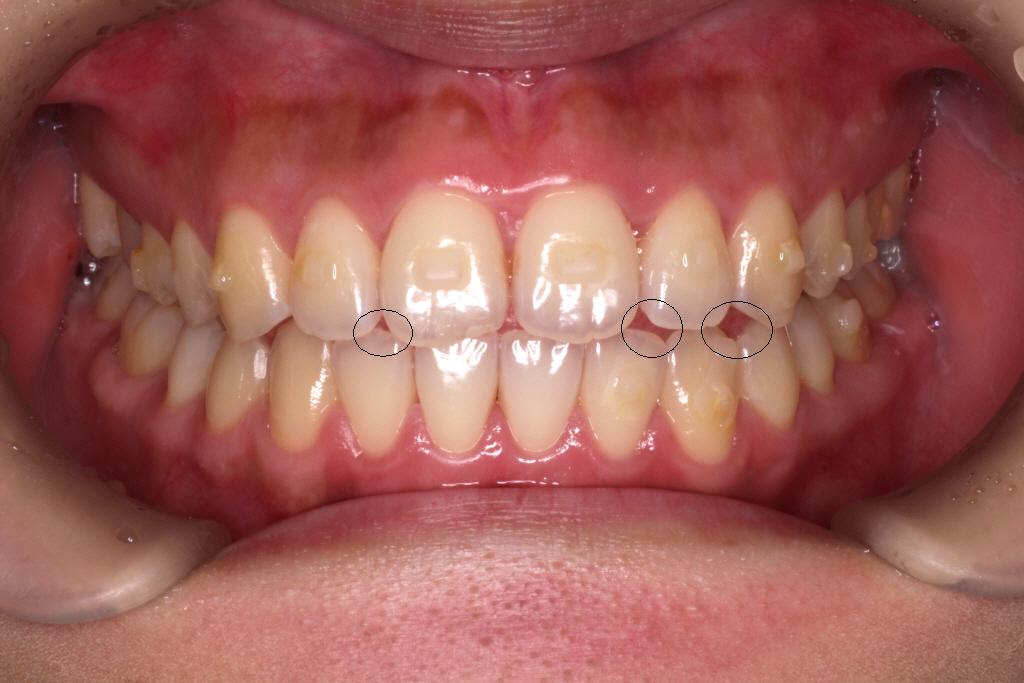

下が1回目のインビザラインが終わった時の写真です。気になっていた前歯のねじれはきれいに並びました。

もう少し噛み合わせを整えるために、アタッチメントを一度全部とりリファイメント(微調整)のお口の型どりをおこないます。

・長期間にわたって重なっていた歯は、歯間接触下部の歯肉組織が失われている場合があり、歯列矯正を行うことで、「ブラックトライアングル」が発生する可能性があります。